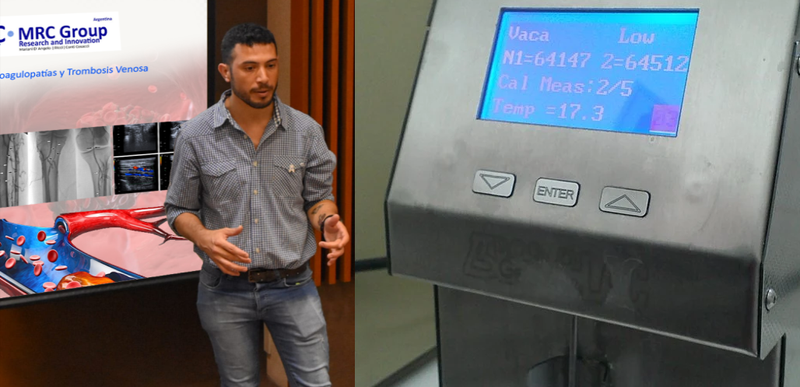

Publicaciones

Las nuevas tecnologías alientan el futuro y brindan un horizonte claro y amigable con el medio ambiente, esa "luz" hacia el final del túnel es parte de un período paradigmático que actualmente ha entrado en una crisis irreversible en relación con el calentamiento global, la disponibilidad de materiales y los costos de producción...

Más informaciónLa reunión sostenida ha sido de gran importancia gracias a la capacidad de R.A.I.S. de entendimiento con los organismos internacionales para alcanzar márgenes de éxito en Asuntos Regulatorios, Legales e Impositivos-Contable.